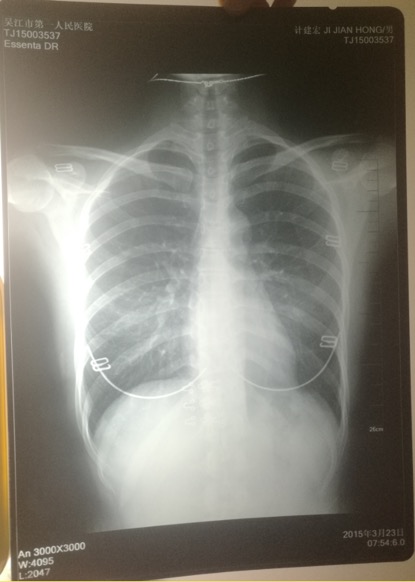

印有計(jì)建宏姓名的胸片實(shí)為一名女性的。 受訪者供圖

印著父親姓名的胸片,圖像卻顯示有明顯女性文胸搭扣和項(xiàng)鏈的印記。

“當(dāng)時(shí)我和母親都奇怪,一年多前體檢正常,怎么這么快腫瘤長(zhǎng)得如此大了?”更令計(jì)云強(qiáng)疑惑的是,該院胸外科主任在系統(tǒng)中輸入計(jì)建宏姓名后,查詢得到的胸片,可明顯看出有女性文胸的搭扣和項(xiàng)鏈,“后來(lái)醫(yī)生含糊地說(shuō)可能是同名同姓,便不讓我看了!

“7月初,我們回到吳江,帶著滿心悲傷和疑慮去了體檢科,想搞清楚父親的胸片究竟是怎么回事!庇(jì)云強(qiáng)稱,此后幾經(jīng)周折,在找了吳江區(qū)第一人民醫(yī)院體檢科、投訴科等多個(gè)部門后,耗時(shí)多月,才被體檢科通知去拿父親的胸片,“一張是我父親的名字,但有文胸印記;另一張是醫(yī)院所謂的我父親的胸片,顯示的是其他人的姓名!